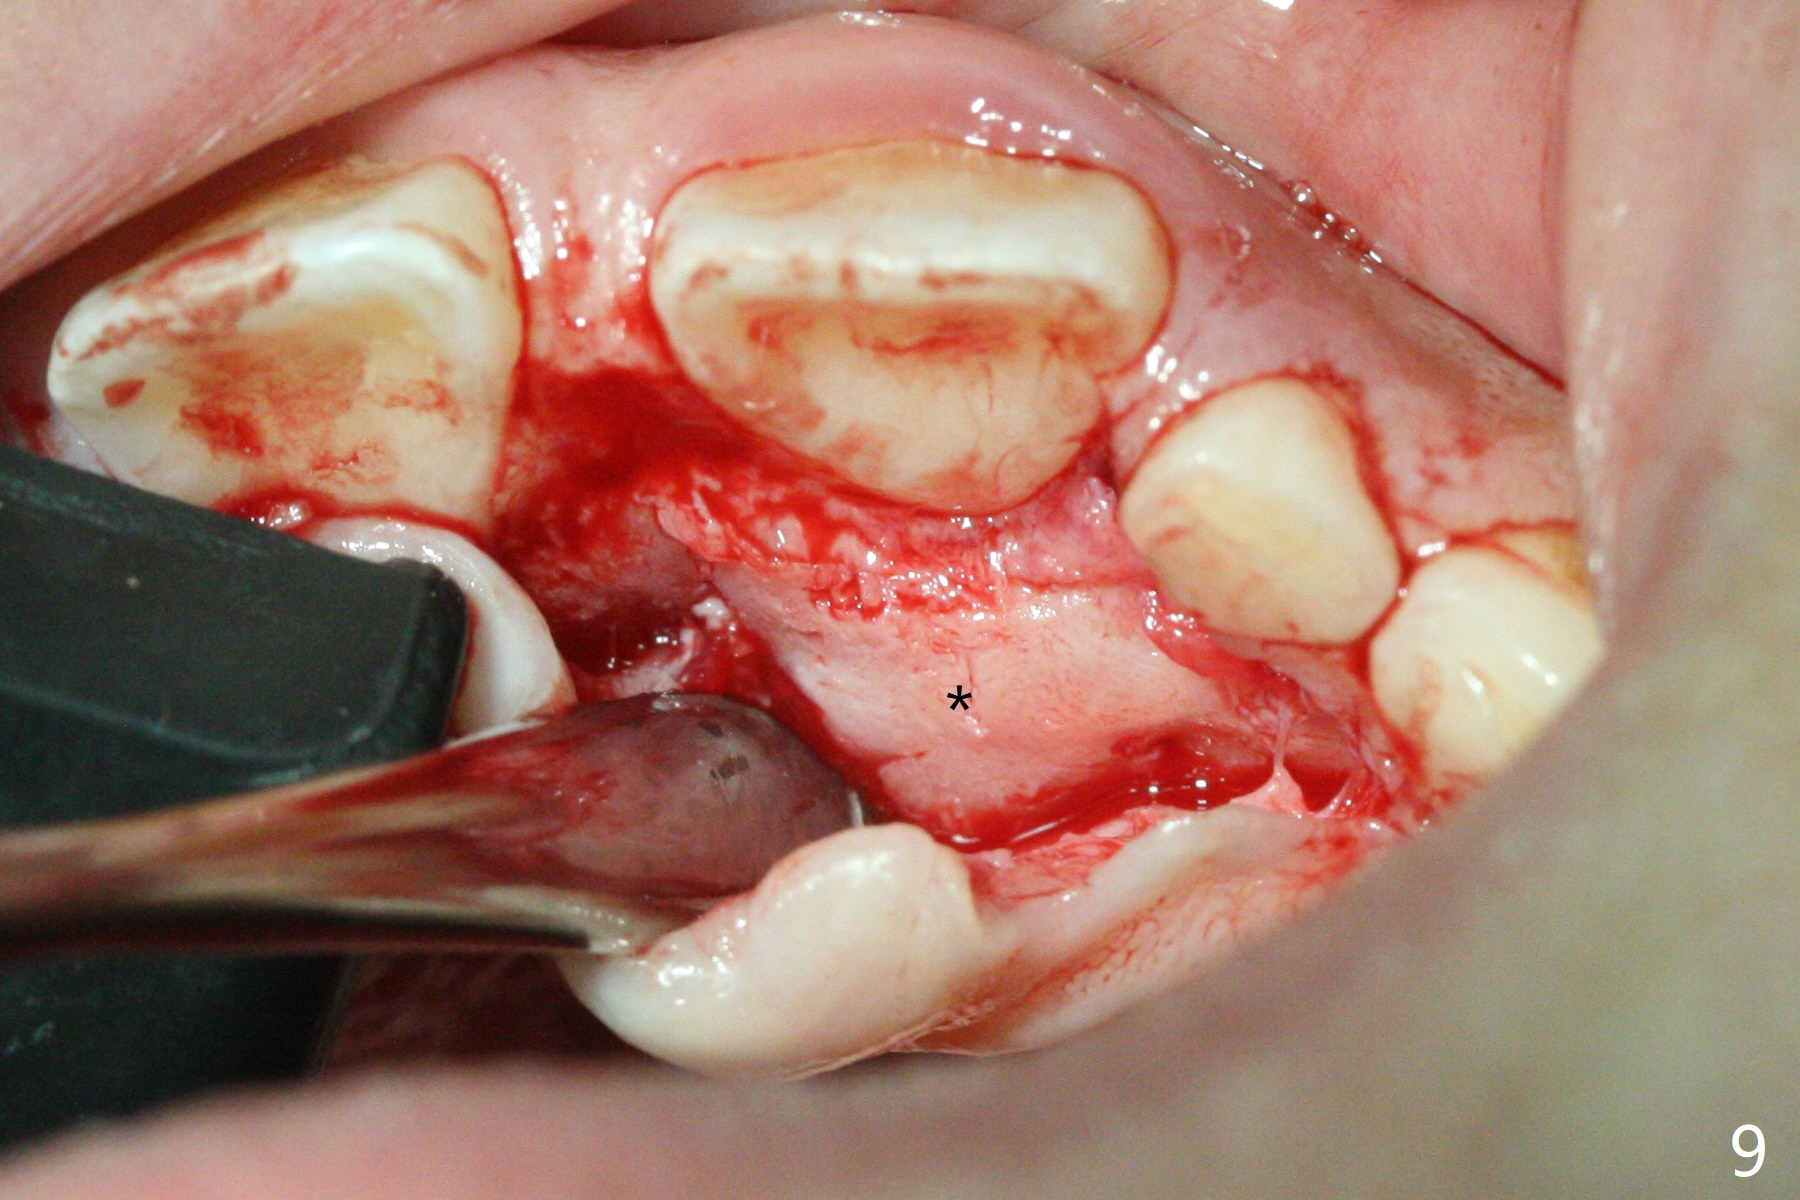

There is a large diastema between the upper central incisors (Fig.7). The left anterior palate is slightly elevated (Fig.8 *). In fact the cortex overlying the mesiodens (Fig. 9 *, 11 <) is to be removed with a surgical handpiece in order to extract the mesiodens (Fig.10). The left central shifts mesial in 7.5 months postop, whereas the right one remains in place (Fig.12). The tooth #7 is unerupted 1 year 4 months postop (Fig.13).